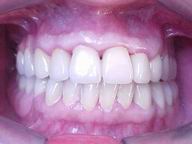

Reabilitação funcional e estética em ambas as arcadas

com próteses fixas e removíveis de encaixe de precisão.

DEPOIS